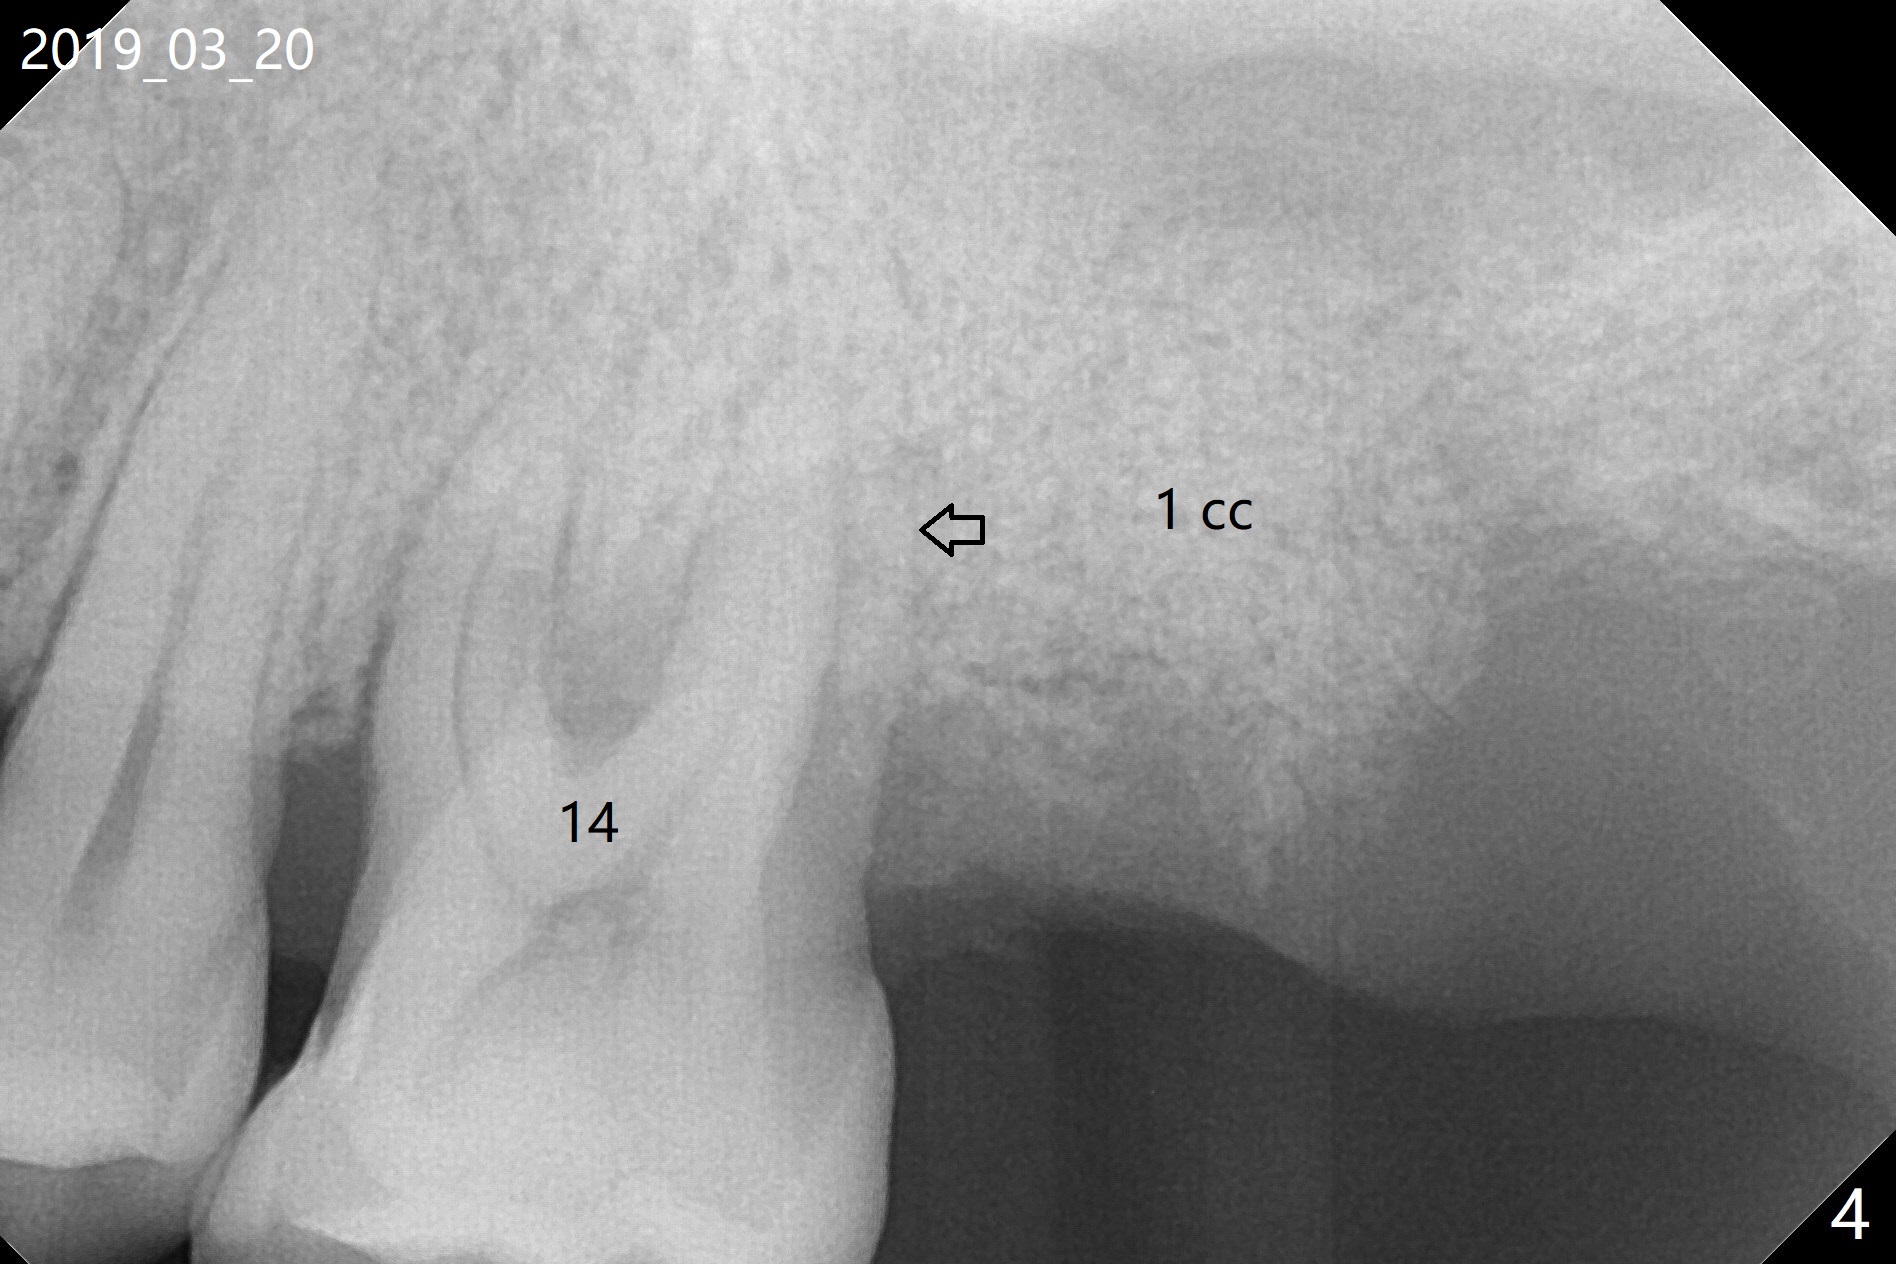

A 54-year-old man returns to clinic 5 months post SRP with chief complaint of UL loose tooth (#15, Fig.1). Since the remaining bone is limited after extraction, it is apparently unsuitable for immediate implant (Fig.2). Socket preservation seems to be able to gain bone height near gingival margin (Fig.3 red line). In fact 1 cc of cortical and cancellous bone mixture is used; after heavy debridement the bone graft is deposited on the distal root surface of the tooth #14 (Fig.4 arrow). The bone increases not only coronally, but also apically (Fig.5 blue lines, as compared to red lines denoting the original bone height). The bone reduces in height 10 months postop (Fig.6). Sinus lift is required for placement of a short implant (Fig.7). Socket preservation does not prevent post-extraction bone loss.